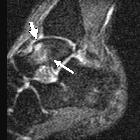

Bone stress

injury of the ankle in professional ballet dancers seen on MRI. Sagittal STIR MR image of a 25-year-old male shows patchy edema signal within the body of the talus (long arrow), which extends to the subchondral region of the talar dome (short arrow). This same edema pattern was observed in nine of the twelve ankles and may be related to chronic repetitive stress.